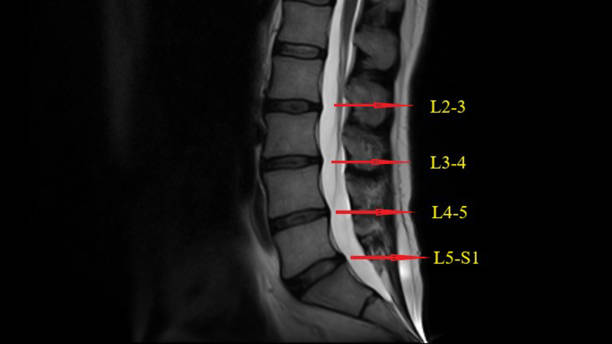

척추협착증은 척추의 추간공이 좁아져 척추 신경이 압박되는 질환입니다.

이로 인해 통증, 저림증, 근력 약화 등의 증상이 나타납니다. 이번 글에서는 척추협착증을 치료하기 위한 다양한 방법을 알려드리겠습니다.